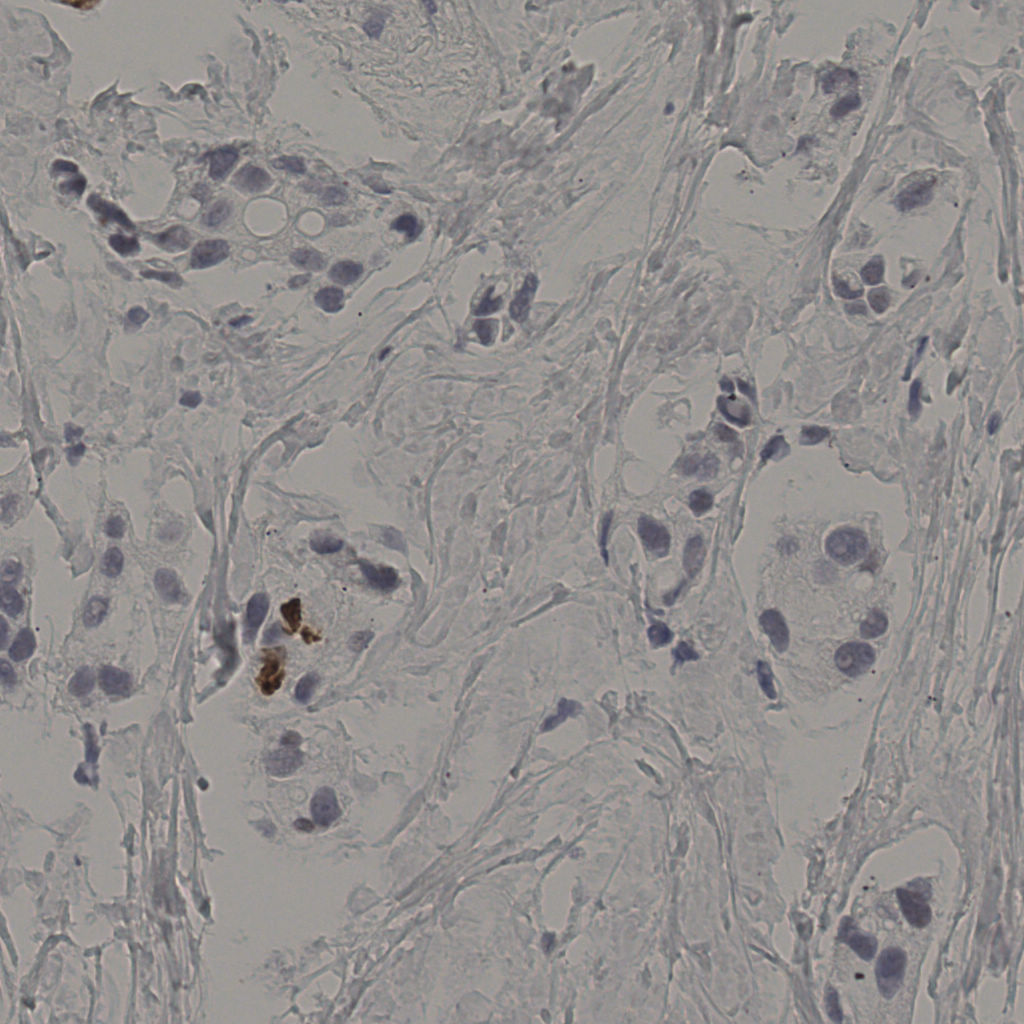

5.31%

Ki67 指数

阴 19502 阳 1093

20240398Ki-67.ndpi

slice_34_12_x30464_y10752.png

slice_34_12_x3046...